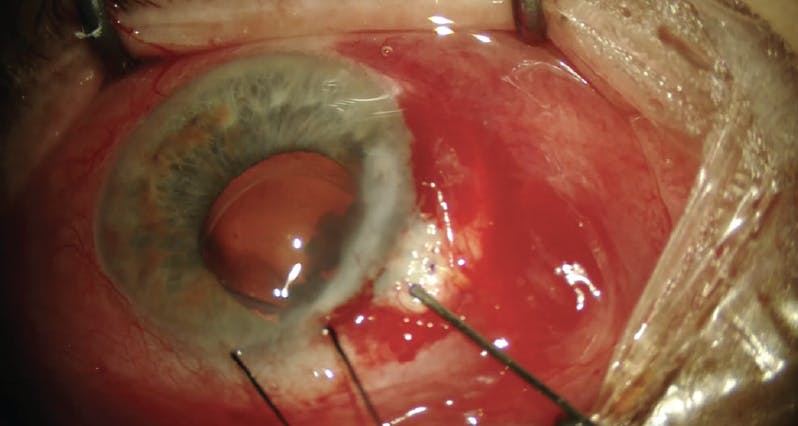

An 81-year-old woman with a history of traumatic glaucoma began experiencing significant side effects of drop use. She was already using all five classes of topical glaucoma medication and had developed notable injection and follicular conjunctivitis in the left eye. Given this, the decision was made to proceed with filtration surgery despite the high-risk status of this eye.

The patient had previously undergone superior scleral tunnel–based cataract surgery, and it was clear, during the initial conjunctival evaluation, that the earlier procedure would create problems at the 12 o’clock region. Attention was therefore turned to the superonasal conjunctiva, where dissection revealed scarring in all directions. A significant amount of this scarring was broken during dissection, and an adequate pocket was created for the creation of a bleb.

A sclerotomy was performed with a 27-gauge needle directed into the (anticipated) midanterior chamber. Due to the past trauma, this eye had a complete loss of superonasal iris tissue. Most of the iris was plastered up against the cornea chronically, creating essentially one large anterior chamber–sulcus space.

Placement of a Xen Gel Stent (Allergan/AbbVie) through the initial sclerotomy became problematic when the device encountered a significant amount of residual, traumatized, and broken fragments of iris tissue. The implant was removed, and a second needle tract was made adjacent to the initial one. This time, the 27-gauge needle tract was created with a slightly exaggerated posterior aim given the large amount of space available (Figure).

Figure. Placement of a Xen Gel Stent (Allergan/AbbVie) became problematic when the device encountered a significant amount of residual, traumatized, and broken fragments of iris tissue in an eye with traumatic glaucoma. A second sclerotomy tract was created using a 27-gauge needle, but insertion was still difficult.

It was difficult to place the hydrated Xen through the 27-gauge needle tract. Although possible, damage to the Xen can occur as continuous manipulation is performed. A 25-gauge needle was therefore used to enlarge the previously placed second 27-gauge needle tract. Even with this enlarged sclerotomy, threading the Xen Gel Stent through the tract was challenging.

Final placement of the implant was excellent. Internally, the Xen was in a large pocket of open space without any concern for potential blockage. Externally, it was mobile and fishtailed freely without incarceration within the Tenon tissue.